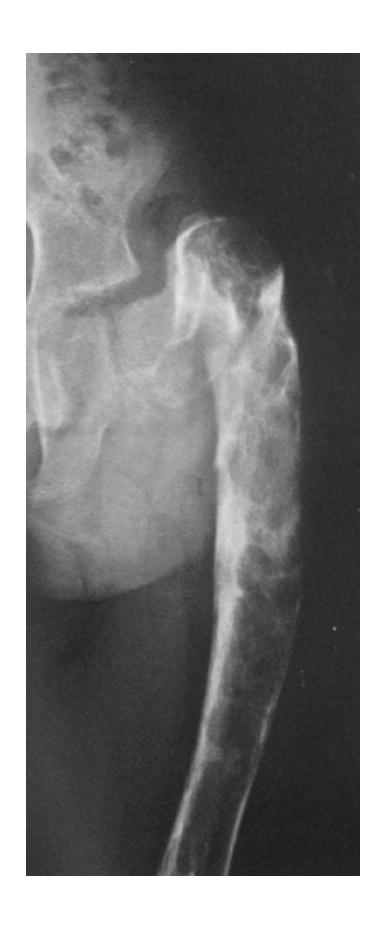

Clinical Case Study

A 50-year-old male tripped over the edge of carpet at home. He heard a crack and is unable to walk. He gave history of progressive weight loss. On clinical examination, he was in pain with a deformity at upper right thigh. He looks pale.

What are the key x-ray findings?

- Decreased bone density in the right proximal femur

- Fracture in the neck of the femur

- AP view of the right proximal femur

What is the diagnosis?

- Pathological fracture due to osteoporosis